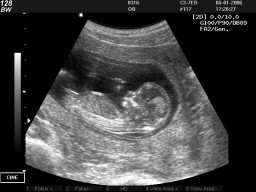

Давайте разбираться объективно, опираясь не на слухи и догадки, а на научные факты и Ваши школьные знания. Начнем с воспоминания того что такое звук и какова его природа.Подробнее